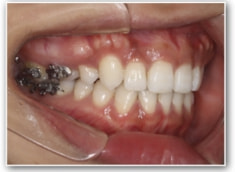

叢生+左下1番先天欠如ケース

治療法:裏側の矯正(リンガルブラケット:舌側矯正)

治療後